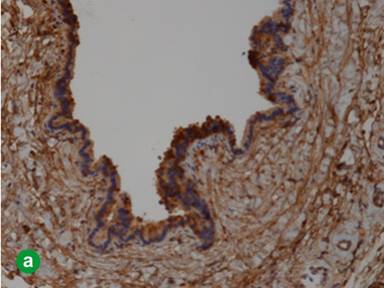

The cystic lining cells were focally reactive to CK7 and Trypsin (Figure 6a) but negative for calretinin, WT1, PAX8, CD31, and CK20. The luminal border of the epithelium was also reactive to EMA. Histochemical staining for PAS was negative in the epithelium. The residual pancreatic islet could be highlighted by IHC stain for synaptophysin (Figure 6b). The whole picture was more like a rare acinar cell cystadenoma.

Figure 6. a. The lining cells were reactive to Trypsin. b. The residual islets of Langerhans (arrow) were positive for synaptophysin, but the lining epithelium was negative. |